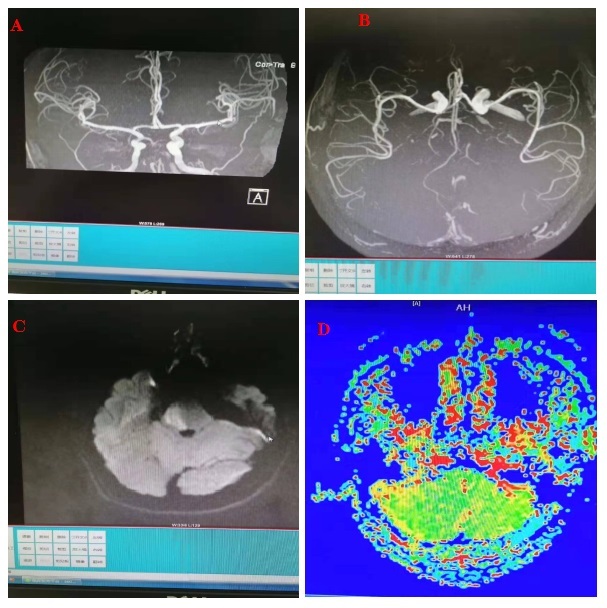

MRA(图A,B)提示基底动脉闭塞可能,DWI(图C)提示脑干梗死,小脑未见梗死病灶,PWI(图D)提示小脑等后循环区域存在低灌注,发现存在不匹配(mismatch)。